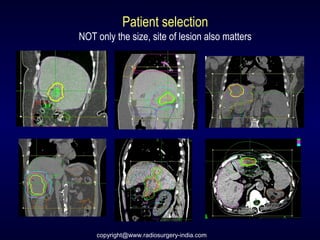

Patient selection

NOT only the size, site of lesion also matters

copyright@www.radiosurgery-india.com